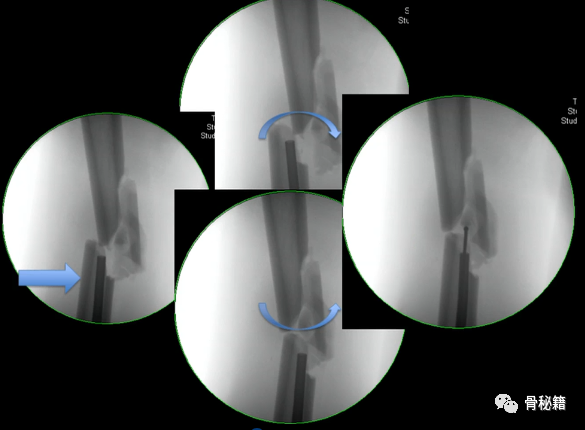

4、注意旋转。有的时候我们不太注意这个问题,有的时候中间比较粉碎,旋转容易忽略,一般来说是保持一个标准正位,近端是看小粗隆的形态,大约露出1/3-2/3,远端是看髌骨在不在两个股骨髁的中间

该例患者在复位置钉后发现远端髌骨不在股骨髁的中心,后进行旋转调整。

6最后提一点锁钉的小技巧,不要造成主任打主钉5分钟,我们锁钉2小时。我们透视的时候,要把锁定空透成两个圆形,但是在操作中往往是椭圆形,这个时候根据椭圆形的长轴来方向来移动C臂,就可以透一个好的圆形了,在此情况下完成锁钉就相对容易些。